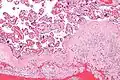

-

Acute choriodeciduitis, with neutrophils seen in the chorion and decidua.

A long-lasting infection of the decidua, chronic deciduitis, is associated with pre-term labour.[4]